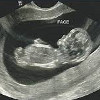

УЗИ 2 четверти. Плановое исследование, которое проводится в течение 20-22 недель, показывает структуру и положение плаценты, пуповины, шейки матки, размер плода, структуру и функционирование его внутренних органов. Это позволяет диагностировать риск выкидыша, замедленного развития и анатомических нарушений плода, плацентарной недостаточности, патологии пуповины. Процедура проводится при многоплодной и однократной беременности в режиме 2D. Стоимость скрининга зависит от количества фруктов.

Стандартный ультразвуковой скрининг на 2 триместра - это 2D исследование. Размер плода, строение органов и костей, образование плаценты, расположение и структура пуповины, количество околоплодных вод определяются. При необходимости проводится дополнительное ультразвуковое сканирование в трехмерном и четырехмерном режиме, допплерография и эхокардиография плода. Во время скринингового обследования во 2-м триместре могут быть выявлены следующие патологии:• Неправильная презентация плода. Аномальная распространенность у плода считается тазовой (ягодицы или ноги опущены), косой и поперечной (с отклонением оси плода, проходящей через затылок и ягодицы, от продольной оси матки). До 30-32 недель неправильное, то есть не проявление головной боли, оценивается как ситуация, требующая наблюдения, поскольку ребенок может повернуться в правильное положение или остаться в том же положении.